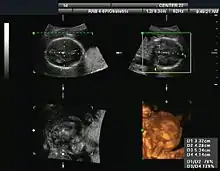

Three-dimensional imaging is done by combining B-mode images, using dedicated rotating or stationary probes. This has also been referred to as C-mode.[4]

To generate a 2-D image, the ultrasonic beam is swept. A transducer may be swept mechanically by rotating or swinging or a 1-D phased array transducer may be used to sweep the beam electronically. The received data is processed and used to construct the image. The image is then a 2-D representation of the slice into the body.

3-D images can be generated by acquiring a series of adjacent 2-D images. Commonly a specialized probe that mechanically scans a conventional 2-D image transducer is used. However, since the mechanical scanning is slow, it is difficult to make 3D images of moving tissues. Recently, 2-D phased array transducers that can sweep the beam in 3-D have been developed. These can image faster and can even be used to make live 3-D images of a beating heart.

Expansions

An additional expansion of ultrasound is bi-planar ultrasound, in which the probe has two 2D planes perpendicular to each other, providing more efficient localization and detection.[53] Furthermore, an omniplane probe can rotate 180° to obtain multiple images.[53] In 3D ultrasound, many 2D planes are digitally added together to create a 3-dimensional image of the object.